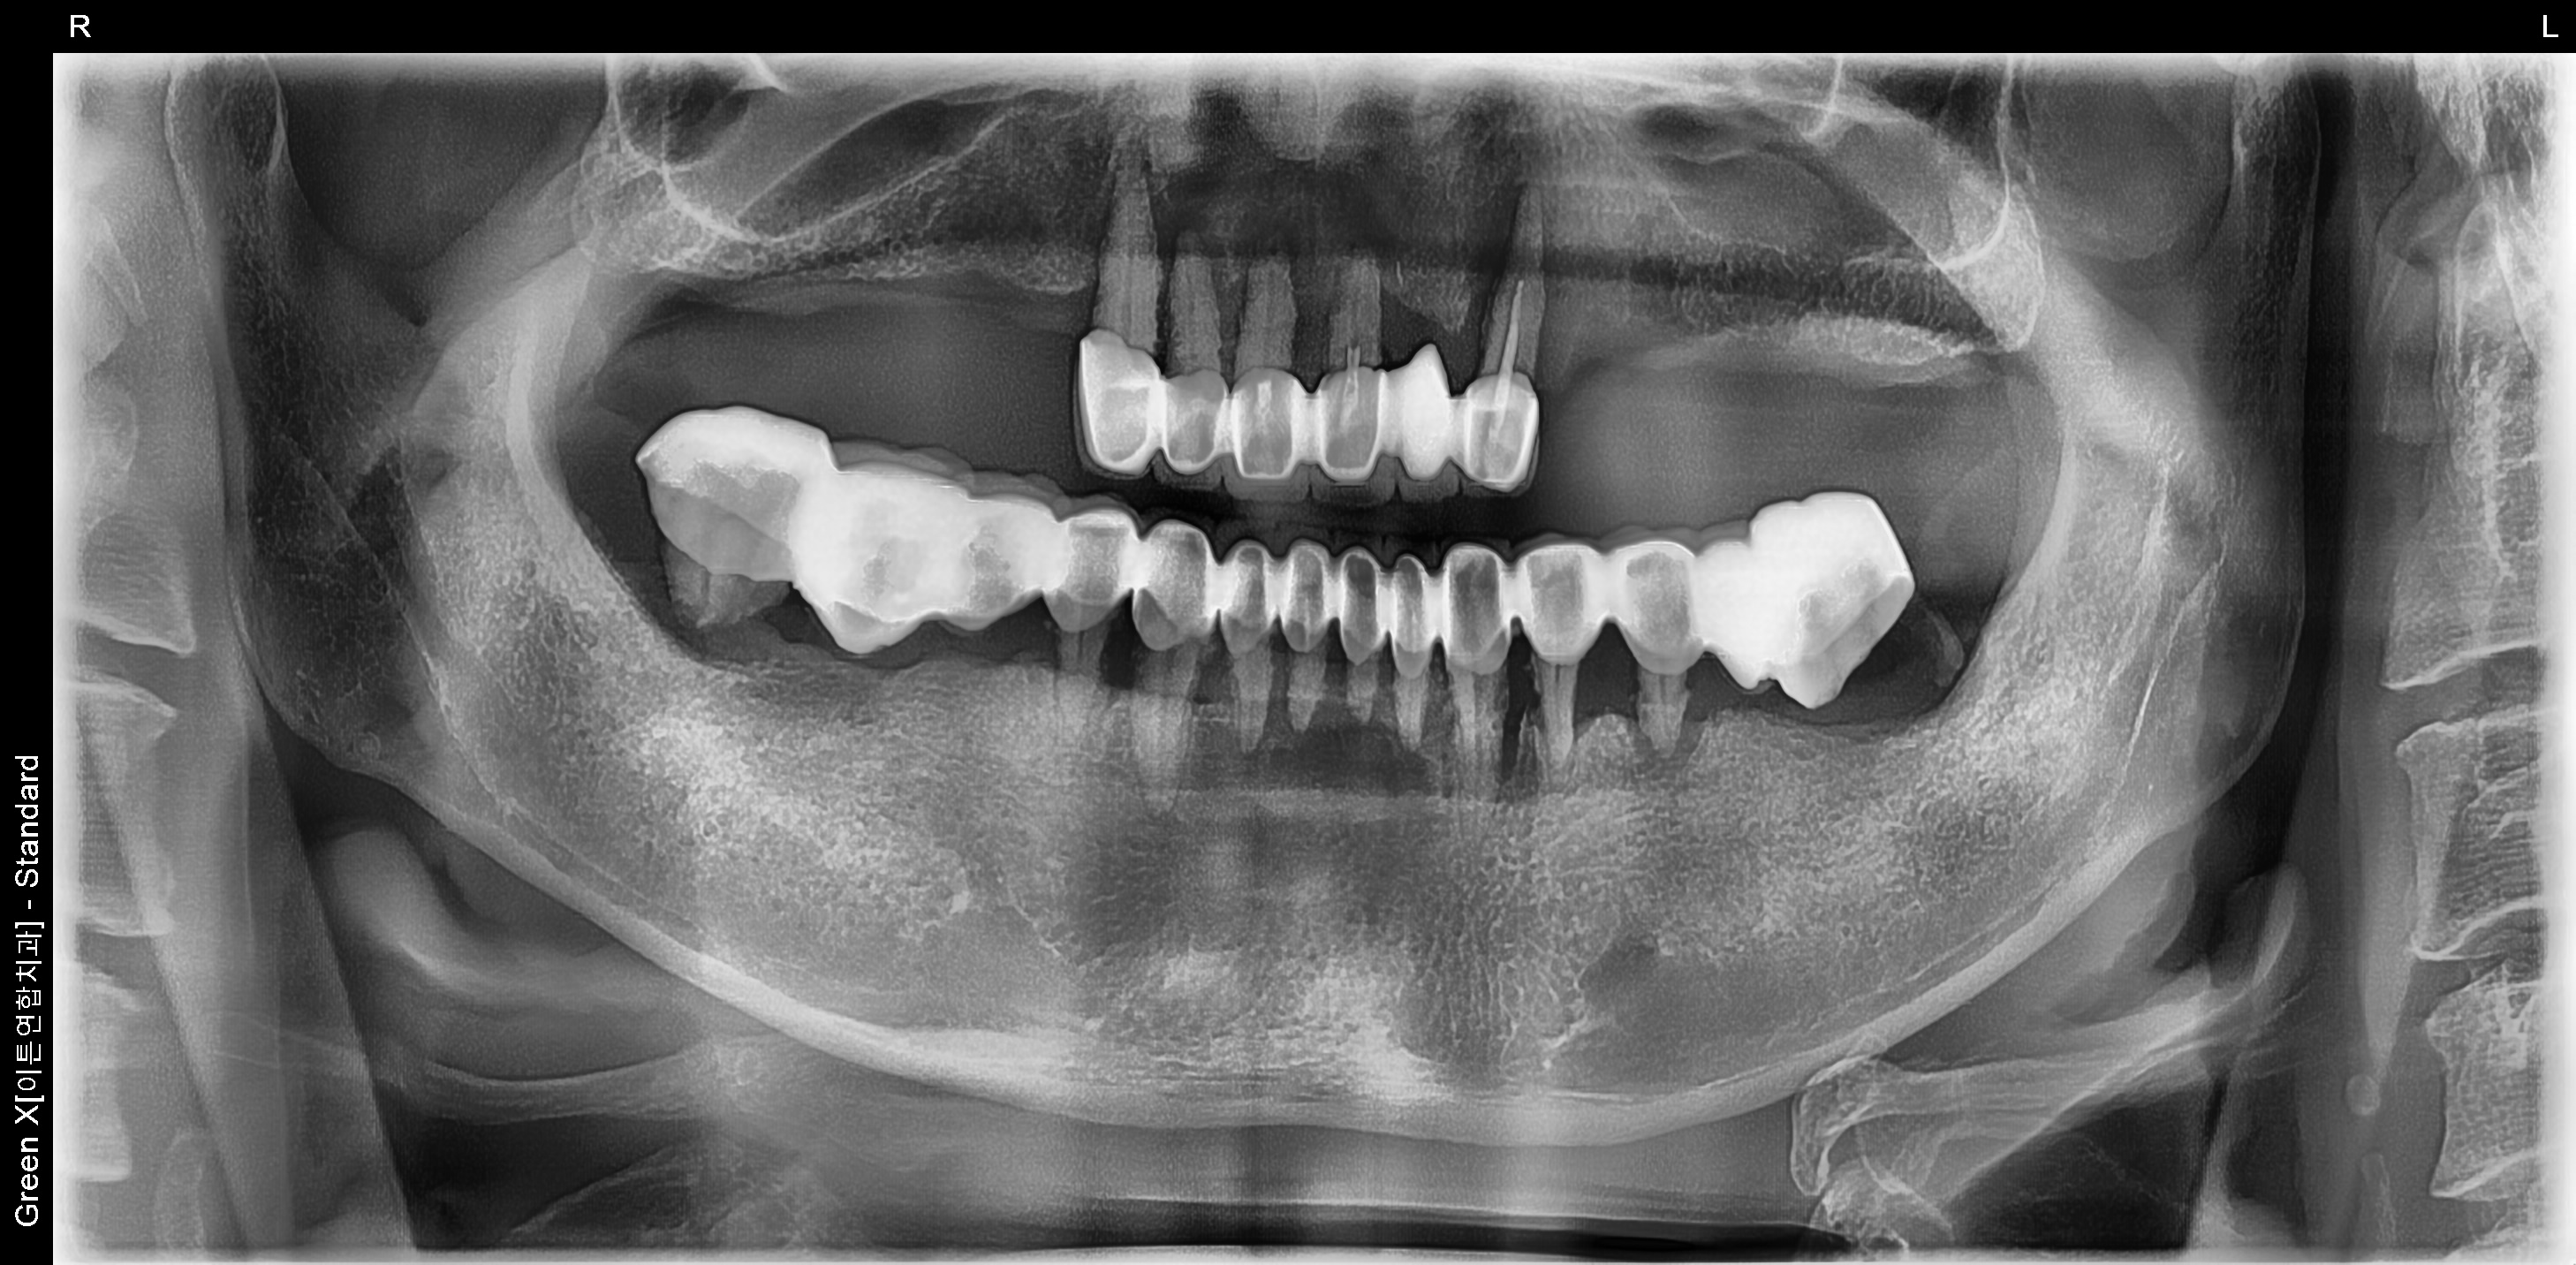

*해당 이미지는 의료법 제57조 동법 시행령을 준수하여 본원에서 직접 촬영했습니다.

치료 전후 사진은 환자분의 동의하에 동일 조건, 인물을 촬영 한 사진을 인위적인

수정 없이 사용해 일반적인 치과 치료 정보를 제공할 목적으로 게시되었습니다.

모든 시술은 개인에 따라 차이가 있을 수 있으며, 부작용이 발생할 수 있으니 의료진과

충분한 상담 후 진행하셔야 합니다.